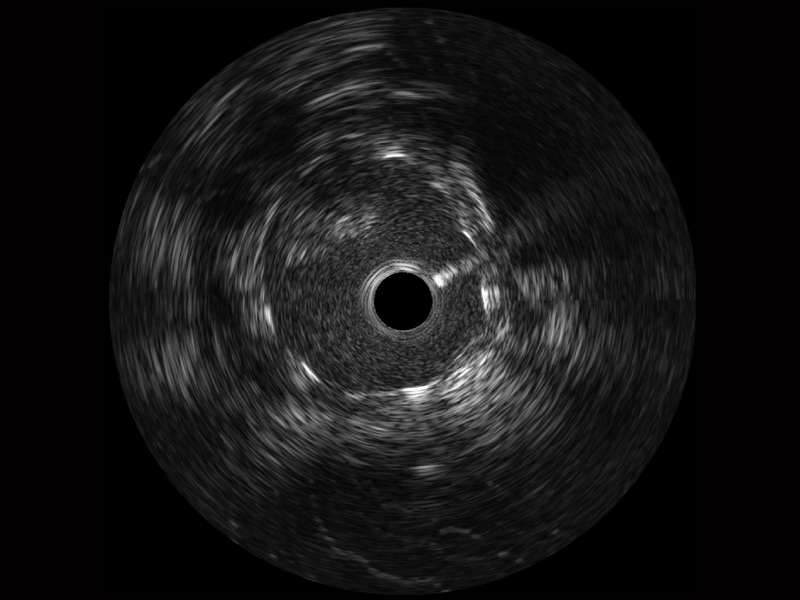

新葡的京集团8814检测站宽频IVUS图像

传统IVUS图像

对比传统IVUS导管成像,新葡的京集团8814检测站宽频IVUS图像的近场支架梁显影更细腻,远场中膜外血管仍清晰可辨,兼顾远中近,兼顾分辨力与穿透深度